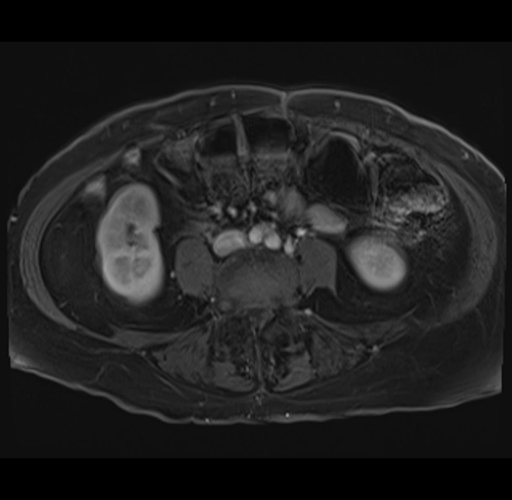

MRI T1